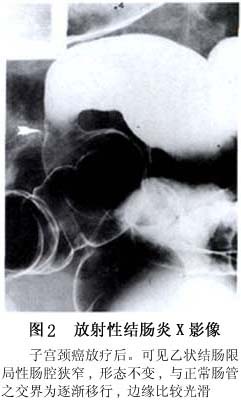

腸道鋇劑檢查有助於病損範圍與性質的確定。但徵象無特異性。在放射性腸炎早期,腹部平片可顯示功能性腸梗阻。鋇劑檢查常顯示黏膜水腫、腸袢擴張和張力減退。在亞急性期,腹壁和腸繫膜都可發生水腫。水腫嚴重時,黏膜皺襞增厚、變直,呈尖聳外觀(spiked appearance),並可使腸袢分開。鋇劑灌腸檢查,在急性期常見結、直腸有嚴重痙攣,直腸前壁可能有孤立性潰瘍。倘有瀰漫性潰瘍存在,結、直腸壁黏膜可呈針刺狀(spicula- tions)。後期慢性放射性小腸結腸炎的鋇劑檢查所見有腸黏膜水腫,腸袢分開。若進一步發生纖維化,則可見腸腔變窄、固定,並呈管狀,可有一段或幾段腸管的擴張性較差,黏膜紋理消失。這種X線表現很像克羅恩病或結腸缺血性病變引起的腸狹窄。由於動力功能障礙,可以發生功能性小腸梗阻。另外,結、直腸病變的X線表現有腸腔狹窄、變直和結腸袋消失等(圖2)。

鋇劑檢查小腸,可見病變常以迴腸末端爲主。充鋇時,可見管腔不規則狹窄,並因粘連而牽拉成角,形成芒刺樣陰影,腸壁增厚、腸曲間距增寬。也可見腸腔結節樣充盈缺損,與炎性腸病相似。排空時小腸正常羽毛狀粘膜紋消失。近年來用腸繫膜血管造影有助於發現小血管病變。對於放射性腸炎的早期診斷與鑑別診斷有一定意義。